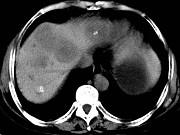

问题 女,55岁,腹胀,肛门闭气,消瘦乏力,肝区疼痛,CT检查如图,最可能的诊断为()

选项 A.多发性肝脓肿 B.肝癌肝内转移 C.肝淋巴管瘤 D.肝脏囊腺瘤 E.结肠癌肝转移

答案 E